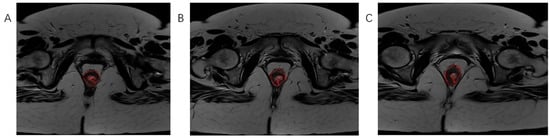

Using software MIPAV (Medical Image Processing, Analysis, and Visualization) version 11.3.2, developed by the National Institutes of Health, Bethesda, MD, USA, histogram analysis was performed on both MRI examinations. All tumor segmentations were performed by a board-certified GI radiologist with 8 years of experience in rectal cancer imaging, blinded to pathological results. Segmentation was performed on T2-weighted axial sequences with regions of interest manually drawn on each slice containing visible tumor while carefully excluding surrounding fat, mesorectal fascia, and bowel lumen. It is followed by volume of interest (VOI) creation and automatically histogram parameter calculation (Figure 3, Figure 4 and Figure 5). The following 7 histogram parameters were measured: mean (average pixel intensity value in the region), standard deviation (measure of pixel intensity variation), median (middle pixel intensity value), kurtosis (measure of distribution “peakedness”), skewness (measure of pixel distribution asymmetry), and 5th and 95th percentiles (markers of distribution extremes). Other than the above-mentioned, other measured morphological, functional, and volumetric parameters are beyond the scope of this study.

Figure 5.

Marking (A) and calculating (B,C) histogram parameters showed on the post-treatment MRI scan, T2-weighted axial sequence.